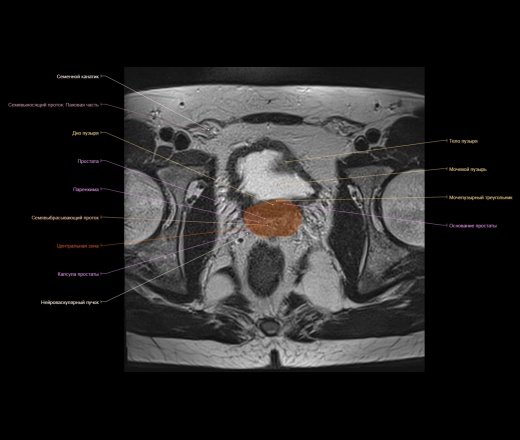

Представленный материал носит обучающий характер, не стал размещать в разделе Презентации, из за отсутствия вьюера с возможностью именно прокручивать изображения как на рабочей станции.

https://www.imaios.com/ru/e-Anatomy/Grudnaya-kletka-bryushnaya-polost-taz/Muzhskoj-taz-MRT

https://radiopaedia.org/cases/normal-prostate-mri

http://event.medradiology.moscow/d/1387577/d/mrt_predstatelnoy_zhelezy.pdf

Надписи очень плохо видно, разместил в разделе Презентации там видно получше.